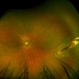

- Patient presenting with globe perforation with a penetration seen at below the inferior arcade with some scattered hemorrhage and a retinal detachment.